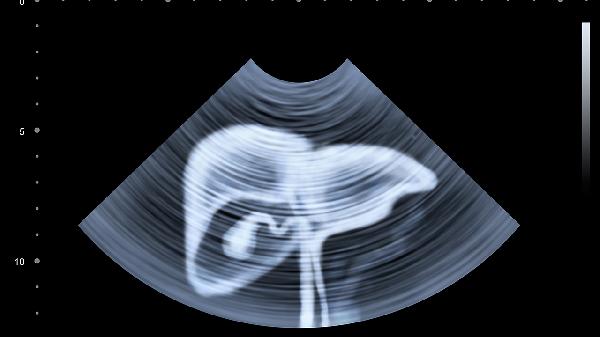

3、定期体检

定期进行肝功能检查和肝脏超声检查,及时发现脂肪肝的进展和并发症。对于高风险人群,如有糖尿病、高血压或肥胖症的患者,更应加强监测。